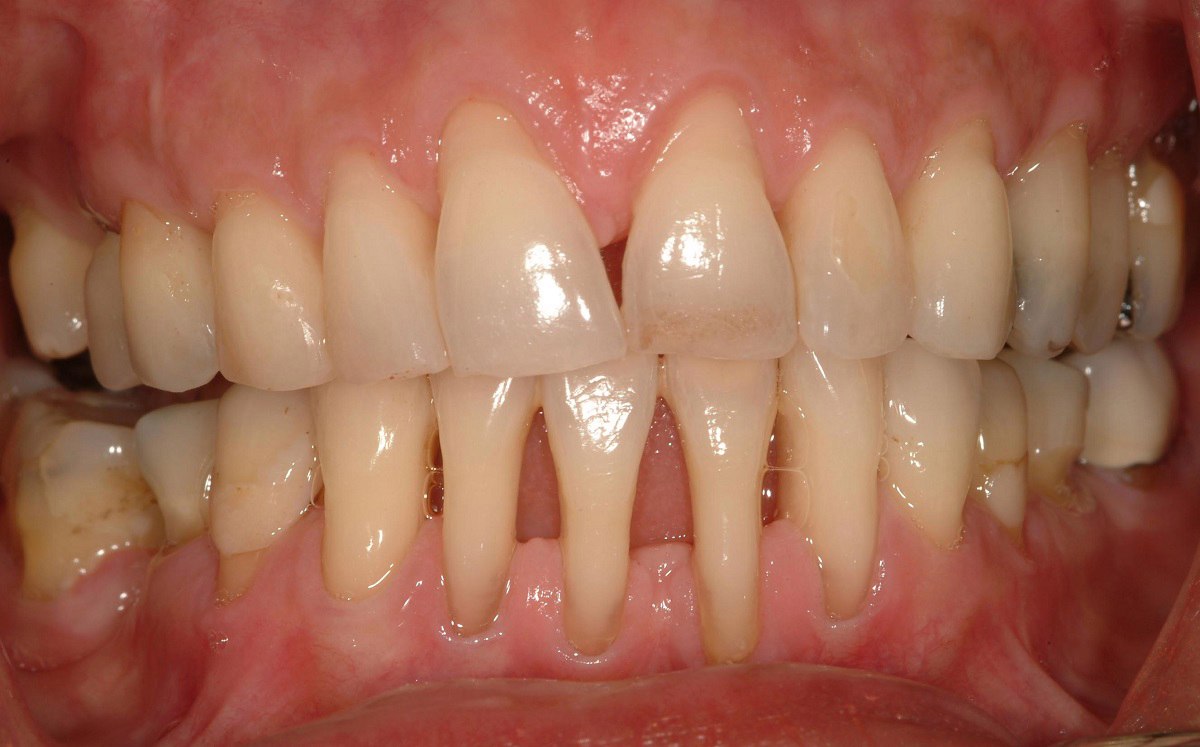

На фотографии показана тяжелая форма периодонтита с серьезной рецессией костной ткани и десен.